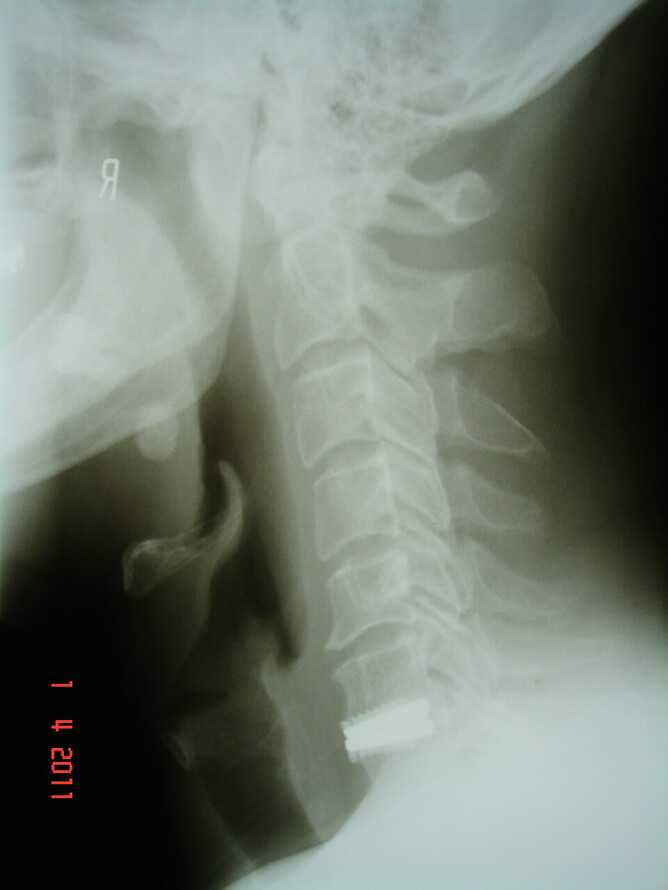

In the past many patients have seen us for pain. They have seen other practitioners and have had Xray’s, MRI’s and/or ultrasounds done in an effort to determine the cause of their complaints. They will often have been told that they have “wear and tear” or “arthritis”, or a “sprained muscle”, but the patient is uncertain what it all means. Patients will ask, “Is that normal”? Or “Is what is seen on the imaging the cause of my pain”? “Why am I still in pain”?

We now offer a service where we will review the presenting complaint and the imaging (Xrays usually) and correlate the symptom to the reports and results of the imaging. We will attempt to answer the questions that the patient has in regard to the report from the specialist and correlate the symptom to the imaging.